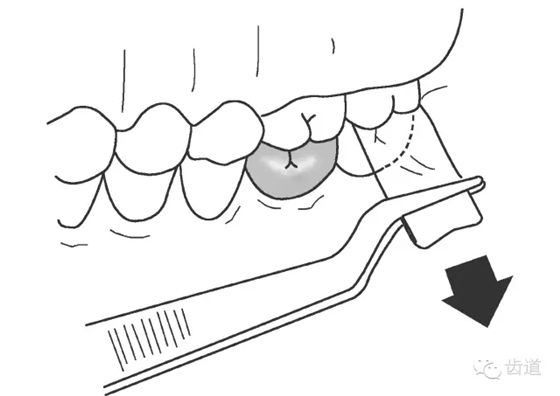

二)邊緣拋光

橡皮杯和浮石拋光冠邊緣

三)口腔衛(wèi)生宣教

牙線清潔冠的近遠(yuǎn)中面,定期檢查